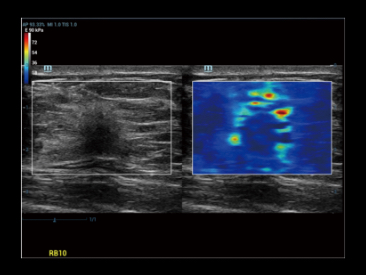

Kompleksowa elastografia odkszta?ceniowa i fali poprzecznej prostaty dla dw├│ch r├│?nych metod biopsji.

Elastografia prostaty: Nowotw├│r prostaty